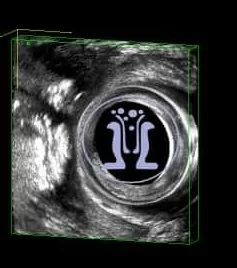

Ενα συριγγιο πρωκτού σε 45 χρονών ασθενή με πολλαπλά δερματικά στόμια δεξιά και αριστερά. Το πρωκτικό στόμιο είναι στην 6η ώρα σε εν τω βαθει επίπεδο, σε απόσταση 21 mm από την είσοδο του δακτυλίου.

Τα στόμια επικοινωνούν μεταξύ των και παρουσιάζουν εκροή υγρού. Η όλη κατάσταση εμφανίσθηκε μετά από παροχέτευση εκτεταμένου περιεδρικού αποστήματος που έδωσε την εντύπωση γάγγραινας Fournier. Η κλινική και υπερηχοτομογραφικη εικόνα ειναι χαρακτηριστική πεταλοειδούς συριγγίου.